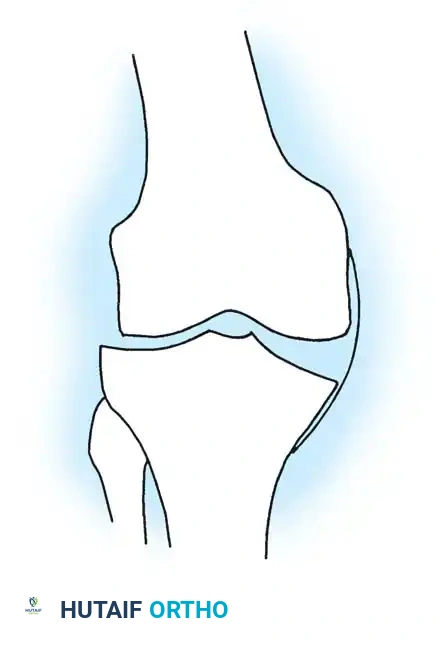

- Ligamentous Tensioning: After component trialing, the joint space kinematics must be assessed. When valgus stress is applied with the knee fully extended, the medial joint space should open exactly 1 to 2 mm. Similarly, the lateral joint space should open 1 to 2 mm under varus stress. Components placed too tightly will cause the tibia to subluxate toward the opposite compartment, producing excessive contact pressures and accelerated polyethylene wear.